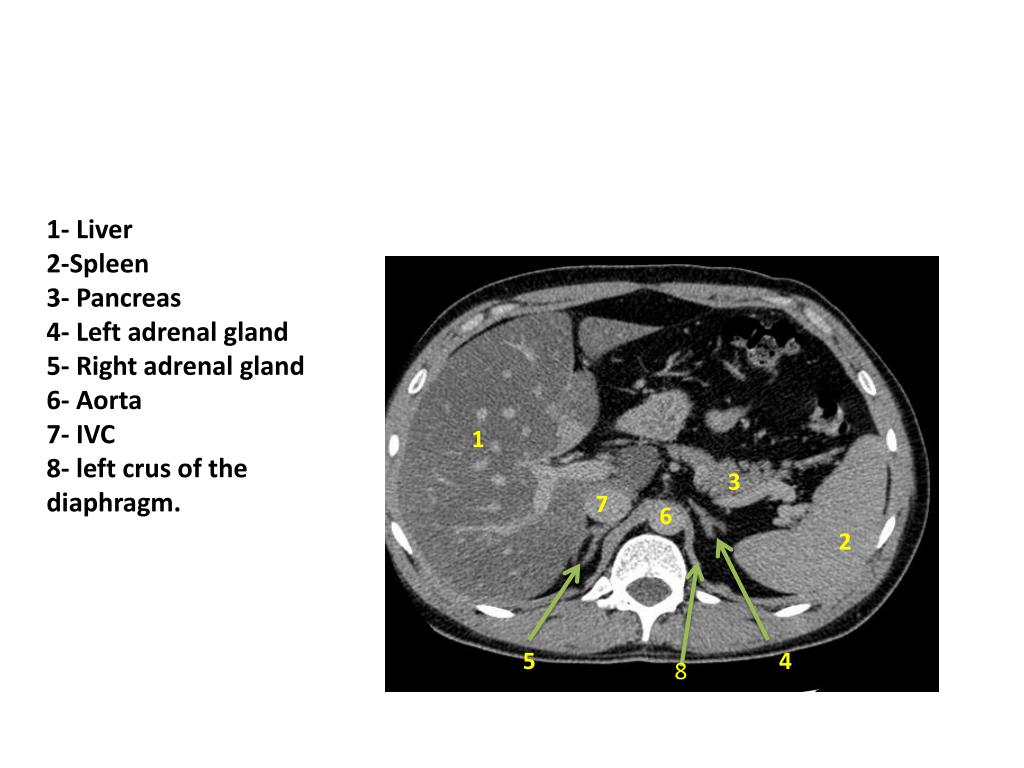

3. 1- Liver 2-Spleen 3- Pancreas 4- Left adrenal gland 5- Right adrenal gland 6- Aorta 7- IVC 8- left crus of the diaphragm. 1 3 7 6 2 5 4 8